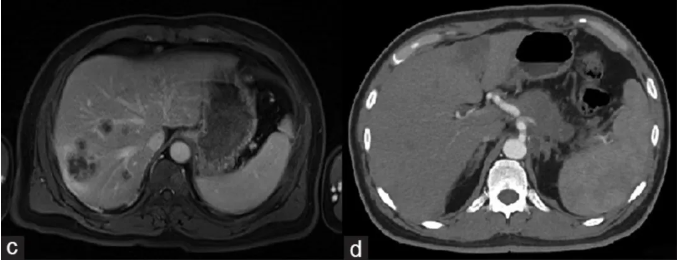

2、腹水改善:治疗过程中,两名患者腹水量显著减少。其中,1002号患者通过计算机断层扫描(CT)成像评估,虽然在治疗前观察到大量腹水,但CAR-NK细胞治疗4个疗程后,腹水量显著减少(详见图2)。而且该患者治疗前腹水呈现乳白色,但在CAR-NK细胞治疗后,腹水变得清晰(详见图3)。

图2 1002号患者治疗前后CT对比

▲图源“Mol Ther”,版权归原作者所有,如无意中侵犯了知识产权,请联系我们删除

3、靶病灶稳定:CT扫描显示,两名患者在基线时以及CAR-NK治疗后2周(患者1001)或4周(患者1002)时,腹膜靶病灶病情稳定。